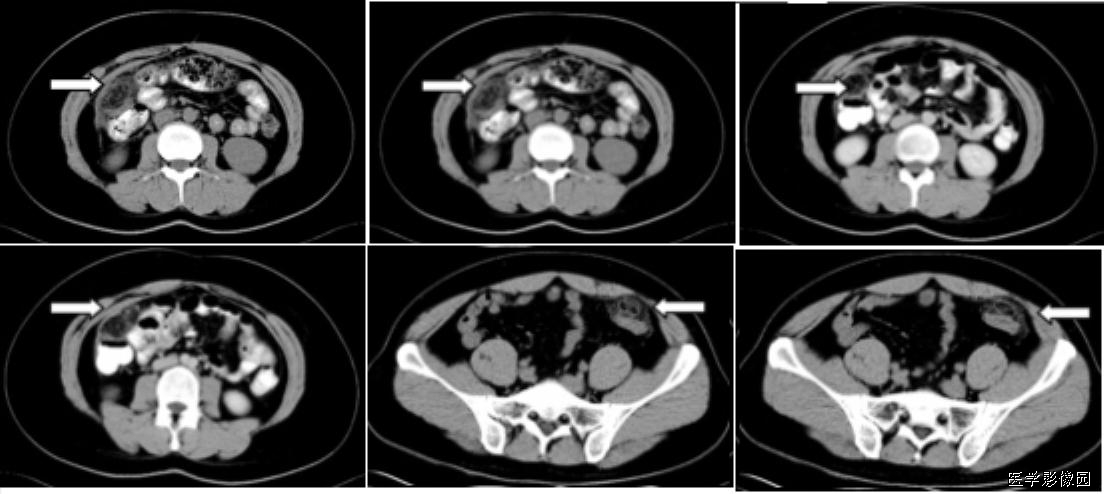

3、不成比例脂肪绞缠征

不成比例脂肪绞缠主要指的是增厚肠壁和周围脂肪在数量方面比例的严重失衡。在少数急性胃肠道疾病中,以肠壁相邻的肠系膜为中心而不是以肠壁为中心,因此肠壁周围脂肪增厚明显高于肠壁厚度。和这一征像相关的疾病主要包括4类:憩室炎、肠脂垂炎、网膜梗死和阑尾炎。胃肠道的大多数炎性疾病包括感染性的、非感染性的和局部缺血性的病变,都是以肠道为中心。这些疾病的肠壁增厚程度往往超过相邻脂肪条索的厚度。但是对于少数以肠壁临近系膜为中心的疾病,脂肪增生明显超过肠壁的厚度。

左上图:右侧腹横肌深面、胆囊内前方梭形囊性病变,有壁但不均匀,略有强化。与腹横肌成锐角,腹横肌肥厚。周围脂肪模糊,有索条点状影。

右上图:邻近降结肠远端系膜壁旁可见一卵圆形类似脂肪密度的病变,周边可见火焰样炎性改变,邻近肠壁有轻微增厚,无明显脓肿及肠梗阻征象。

左下图:肠壁增厚,结肠袋襞显影不良,以及结肠周围脂肪束条状改变。

右下图:CT显示壁明显增强的管状结构(箭头),右中腹的脂肪系膜反应。